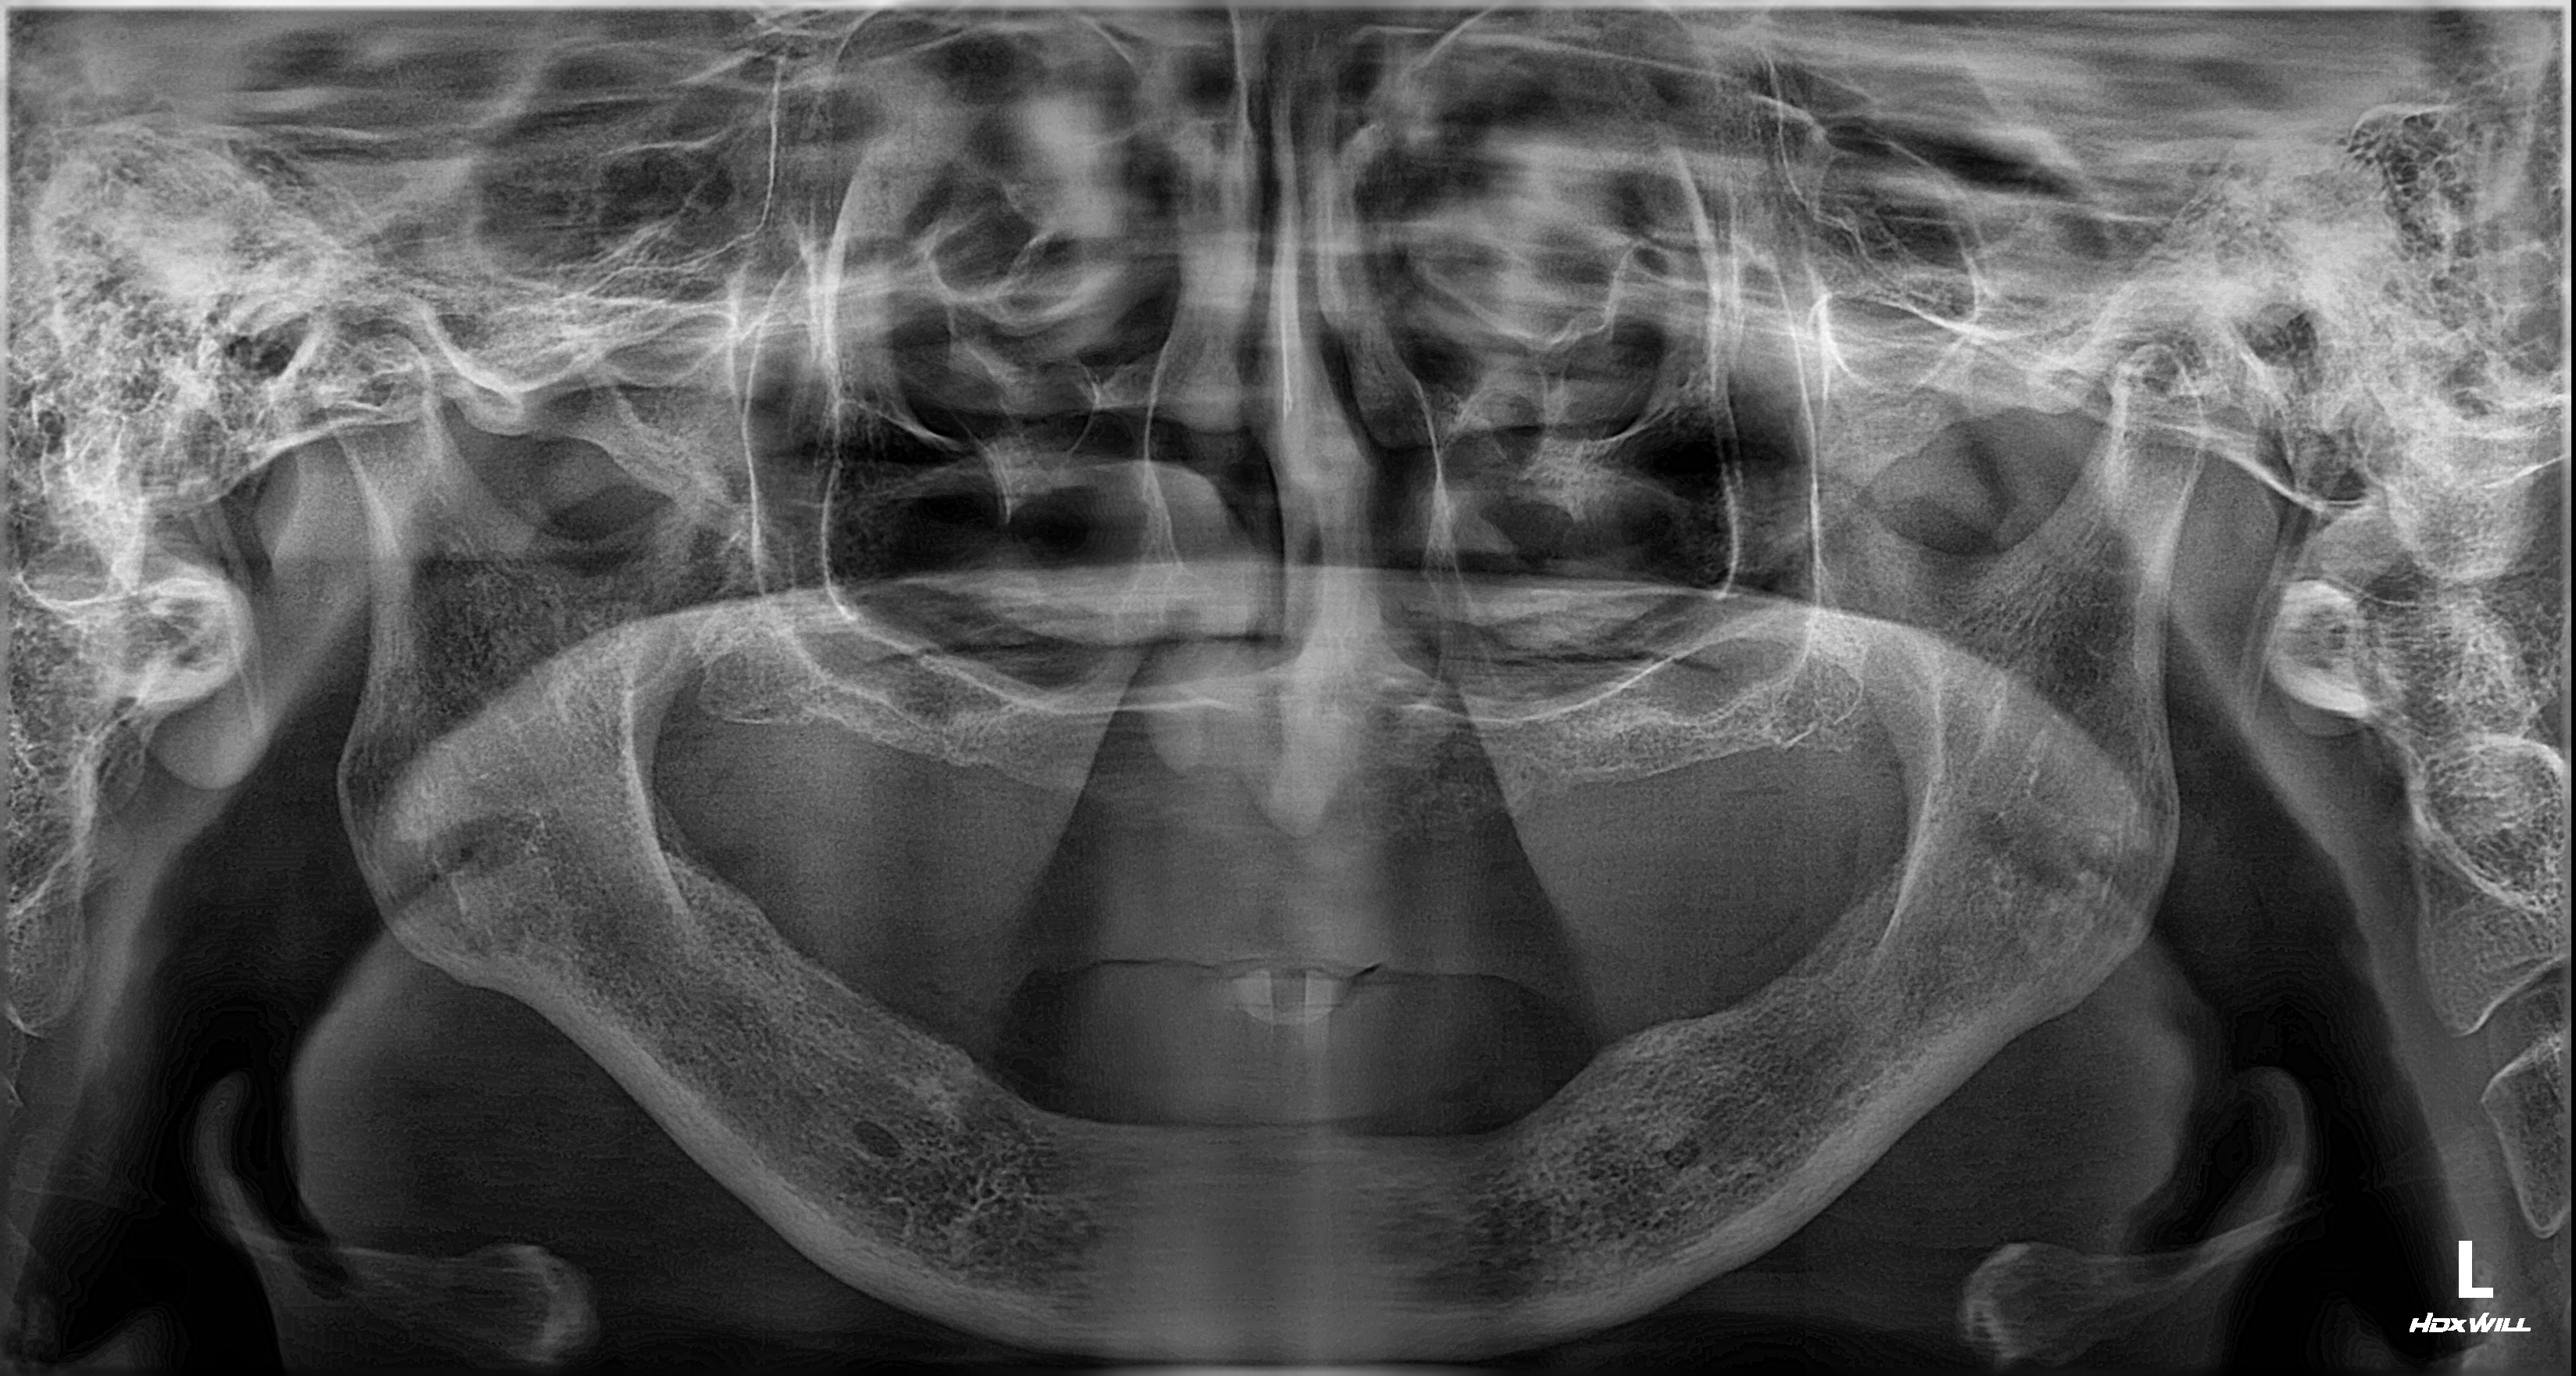

촬영일시: 2026.02.27. [ 치료기간: 2025년 04월 17일 ~2026년 02월 27일 ] ※ 365서울앞선치과의원의 모든 컬럼은 각 진료과 의료진이 직접 작성합니다. 365서울앞선치과의원 임상 케이스 게시물은 환자분께 의학적으로 정확하고 상세한 정보를 드리기 위해 각 진료과 의료진이 직접 작성하며, 모든 증례 사진은 본원 의료진이 직접 시술한 증례를 촬영한 것으로, 의료법 제23조, 제56조에 의거하며 환자분의 동의를 얻어 포스팅에 사용하였습니다. 또한 해당 케이스는 본 환자분의 치료 결과이며, 환자 상태에 따라 치료의 결과는 달라질 수 있습니다. |